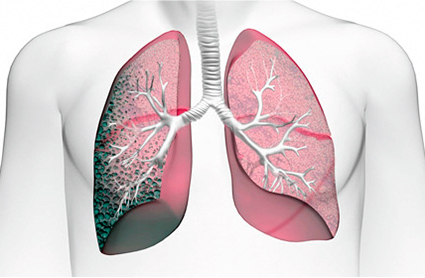

Пневмосклероз легких — это серьезное заболевание, которое вызывает изменения в легочной ткани, приводя к ее уплотнению и снижению функциональности. Люди, столкнувшиеся с этой проблемой, отмечают такие признаки, как одышка, хронический кашель и усталость. На начальных стадиях заболевания симптомы могут быть слабо выражены, что затрудняет диагностику. Лечение пневмосклероза обычно включает медикаментозную терапию, направленную на улучшение дыхательной функции и замедление прогрессирования болезни. В некоторых случаях может потребоваться кислородная терапия или даже хирургическое вмешательство. Продолжительность жизни пациентов зависит от степени поражения легких и своевременности лечения. Многие люди подчеркивают важность регулярных медицинских осмотров и ранней диагностики для повышения качества жизни и продления ее продолжительности.

Постпневмонический пневмосклероз может стать последствием неполного излечения от воспаления легких, что приводит к разрастанию соединительной рубцовой ткани и облитерации просвета альвеол. Также на его возникновение влияют стафилококковые пневмонии, в результате которых образуется некроз легочной паренхимы и формируется абсцесс, при заживлении которого разрастается фиброзная ткань.

Диффузный пневмосклероз с формированием т.н. «сотового легкого», как правило, является следствием фиброзного альвеолита или лучевого поражения.

Диффузный пневмосклероз легких охватывает орган целиком. Иногда он может распространяться одновременно на два легких. При этом виде заболевания ткань легкого меняет свою структуру и теряет эластичность, легкие уменьшаются в размерах. Из-за этого снижается функциональность органа, что приводит к ухудшению работы всего организма. Недостаток кислорода уменьшает работоспособность пациента, приводит к болям в разных органах, обострению хронических заболеваний.

Цирроз. Тяжелая форма пневмосклероза, при которой происходит замещение значительной площади легких соединительной тканью: структуры легочной системы уплотняются и полностью прекращают выполнять свои функции. Органы грудной клетки при этом смещаются, что вызывает дополнительные проявления патологии.